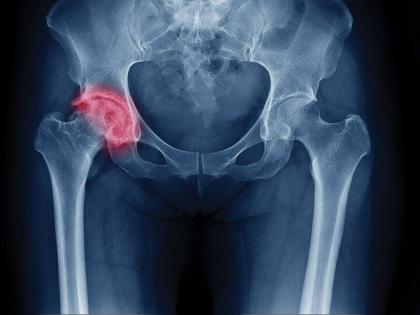

अलिकडे लोक पेनकिलर गोळयांचं अधिक सेवन करतात. त्यात साधारणपणे ट्रामडोलचं सेवन केलं. पण या गोळीचं सेवन अधिक केल्याने हिप फ्रॅक्चरचा धोका वाढू शकतो. नुकत्याच करण्यात आलेल्या एका रिसर्चमध्ये सहभाग घेतलेल्या तज्ज्ञांनी सांगितले की, ट्रामडोलचा वापर काळजीपूर्वक केला पाहिजे. कारण याचं फार जास्त सेवन कराल तर हिप फ्रॅक्टरचं कारण ठरू शकतं. खासकरून ५० पेक्षा अधिक वय असलेल्या लोकांमध्ये ही समस्या अधिक बघितली गेली आहे.

या रिसर्चदरम्यान एक वर्ष फॉलोअपमध्ये १, ४६, ९५६ लोकांपैकी ५१८ लोकांमध्ये हिप फ्रॅक्चर आढळून आला. ज्यामुळे अन्य पेनकिलरच्या तुलनेत ट्राडामोलने हिप फ्रॅक्चरचा धोका अधिक होत असल्याचं सांगण्यात आलं.